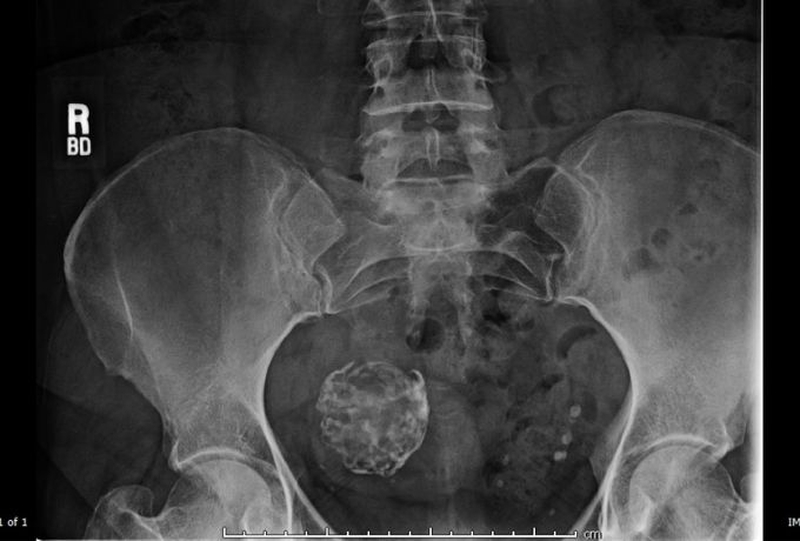

Hình ảnh X - quang của khối u xơ tử cung bị vôi hóa